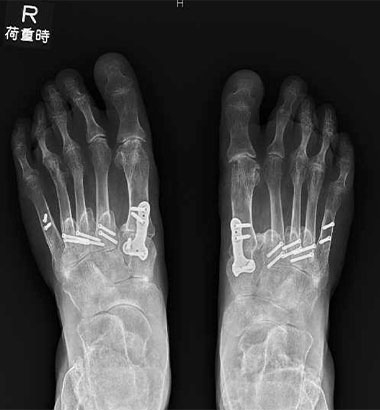

特に重度の外反母趾やリウマチに伴うあしゆび変形に対して、関節を温存しながら機能を再建するための術式として、CMOS(Combination Metatarsal Osteotomies for Shortening)法を導入しています。

CMOS法では、以下のような骨切り術を症例に応じて組み合わせます:

これにより、以下のようなメリットが得られます:

CMOSは、関節を犠牲にせずにあしゆびのバランスと機能を再建できる術式であり、当センターでは、重度変形症例に対して積極的に導入しています。

術前

術後